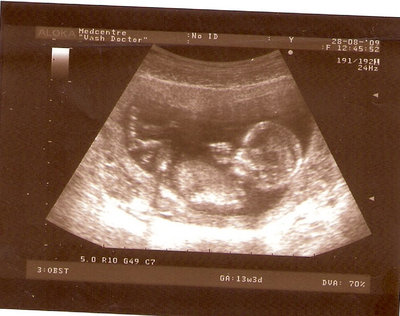

13 НЕД И 5 ДНЕЙ

| Вложения: |

3.jpg [ 96.81 КБ | Просмотров: 2808 ]

Nikisa писал(а): Foto prosto chudesnoe. A na kakom sroke uznali, chto sin.............. НА 13 НЕДЕЛЯХ.КАК РАЗ ВОТ В ЭТО узи, ОНО УМЕНЯ ВТОРОЕ БЫЛО. ЭТО КОНЕЧНО МАЛЕНЬКИЙ СРОК ДЛЯ ОПРЕДЕЛЕНИЯ ПОЛА. НО Я ПОПРОСИЛА ВРАЧА(ЭТО КТСТАТИВ РОССИИ БЫЛО) ХОТЯ БЫ ПРЕДПОЛОЖИТЬ. ЕЙ ВСЁ ТАКИ УДАЛОСЬ РАССМОТРЕТЬ.НУ ВООБЩЕМ ЧЕРЕЗ НЕСКОЛЬ ДНЕЙ ПОЙДУ К ВРАЧУ, УЖЕ АМЕРЕКАНСКОМУ И УЗНАЮ ТОЧНО. К ТОМУ ВРЕМЕНИ У МЕНЯ БУДЕТ СРОК 18 НЕДЕЛЬ. ХОТЕЛОСЬ БЫ ПОСМОТРЕТЬ НА ДРУГИЕ ФОТО НА ЭТОМ СРОКЕ ИЛИ БОЛЬШЕ. ТАК ЧТО ВЫКЛАДЫВАЙТЕ, ЕСЛИ НЕ ЖАЛКО!